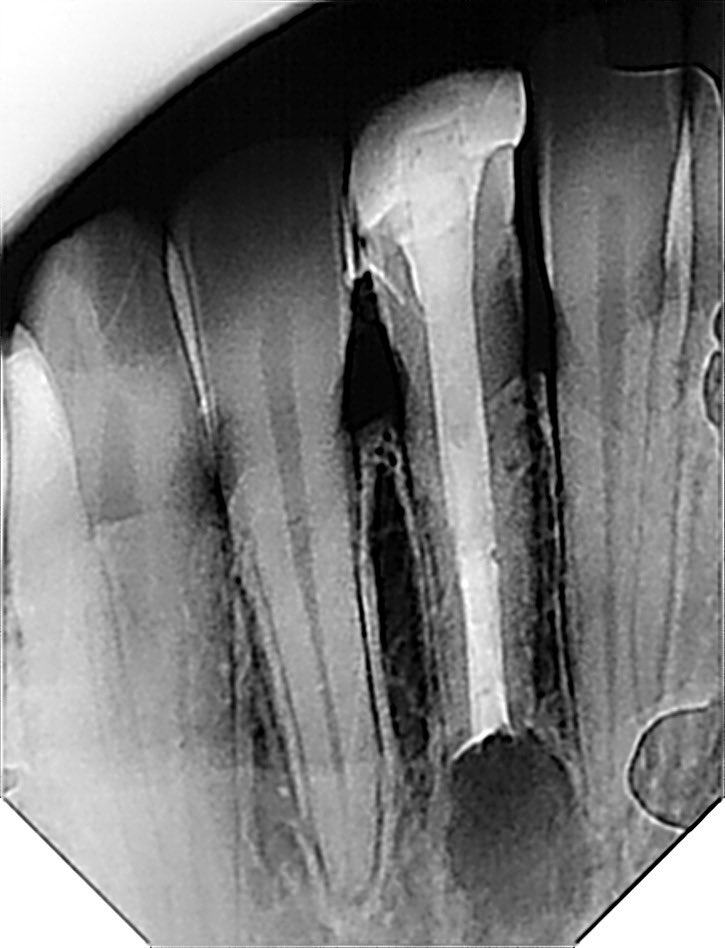

طبيب مقيم في علاج الجذور و عصب الأسنان 🦷 🦷 Endodontic resident at @ksmcmedia 📍Riyadh